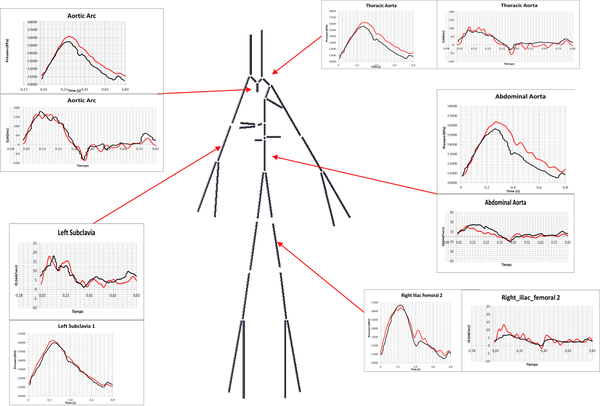

2 A Reduced Order Model based on Coupled 1D/3D Finite Element Simulations for an Efficient Analysis of Hemodynamics Problems

Title: A Reduced Order Model based on Coupled 1D/3D Finite Element Simulations for an Efficient Analysis of Hemodynamics Problems.

Authors: E.Soudah, R.Rossi, S.Idelsohn, E.Oñate.

Journal: Journal of Computational Mechanics. (2014) 54:1013-1022.

Received: 18 February 2014 / Accepted: 30 April 2014 / Published online: 23 May 2014

DOI: 10.1007/s00466-014-1040-2

Scientific contribution: Design of a new methodology to estimate the pressure drop in aortic coarctation under different scenarios. The methodology is based on the integration a 1D numerical model (see appendix 9) into a reduced order model based on 3D CFD formulation.

Contribution to the paper: The principal author developed and implemented the 1D model and the reduced order model into the KRATOS Multi-Physics software (www.cimne.com/kratos)([61]).

In this monograph we have developed a geometrical multiscale framework for simulation cardiovascular diseases under different physiological and pathological conditions. The cardiovascular diseases studied under this multiscale framework were the Aorta Coartaction and Coronary Disease, but, the technology underlying is applicable to other common cardiovascular conditions, including peripheral, cerebrovascular, and reno-vascular disease, and may be used to determine whether vascular stenosis are hemodynamically significant as well as the relative benefit of therapeutic interventions. In this line, we have also proposed a new coronary indicator to evaluate the stenosis without hyperemia condition (under evaluation). At the same time, we have developed and validated a 1D numerical model coupled with the reduced order model. A 1D-reduced order model validation for other groups of people or patients could also be useful for research and clinical outcome analysis. The 1D model is able to describe the pulse wave dynamics and the interaction between the heart and the circulatory system. We have also studied the hemodynamics factors that may be important in triggering the onset of aneurysms correlated with the patient-specific anatomy. The hemodynamics factor and the geometry are directly related with the ILT formation. More AAA cases are needed to define a direct correlation between the hemodynamics factors and AAA development. Quantification of WSS, as well as other WSS-based indicators, are of crucial importance for the understanding of the development of cardiovascular pathologies as, aneurysm or arteriosclerosis. In this way, the feasibility of CFD as a predictive tool to use for treatment planning of cardiovascular diseases has been demonstrated. A methodology to obtain computational meshes from medical image has been defined. A new procedure to segment the aorta using 4D flow CMR data has also been proposed. Beyond this, 4D flow CMR visualization offers a more qualitative and comprehensive description of the flow fields than any other in-vivo imaging technique. The velocity data provided by 4D flow CMR has been complementary to the higher resolution velocity fields computed by the CFD in order to estimate the WSS. We have also developed an algorithm to compute WSS based on the 4D flow CMR data. Based on that approach other diagnostic indicators could be estimated, as pulse wave velocity(PWV)[89], turbulent kinetic energy[90], relative pressure fields[91] or volume and kinetic energy of ventricular flow compartments[92]. For full details refer to the 'Results sections of papers.